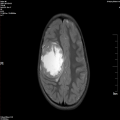

右侧额叶可见一类圆形混杂信号影,边缘光整,最大截面约59.5mm*56.8mm,中线结构明显左偏,增强后,可见边缘强化。右侧额叶占位;胶质瘤?其他?